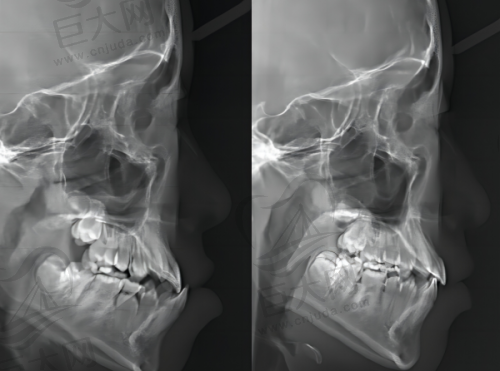

临汾完美齿科注重个性化服务与新型技术的结合。它拥有一支团队,能够为患者提供从常规检查到复杂治疗的多方位服务。这里特别重视患者的舒适体验,医生会根据每位患者的情况进行个性化服务。虽然其室内面积并不大,总共有两层,但医用设备和技术不用担心。张建国作为临汾完美齿科的院长,到现在为止已有14年的工作经验,尤其是在种植牙项目上积累了丰富的治疗技巧。比如在操作过程中,他会根据牙齿的缺失数量、健康状态、以及骨质、骨量、骨密度等多方面因素综合考虑,然后配合相应的治疗。